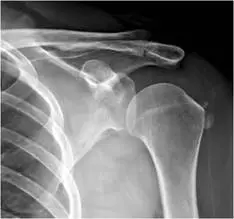

59 歲女性一個月前跌倒後出現左肩疼痛的症狀,影響睡眠,肩關節 X光檢查如附圖,最可能的診斷為何?

本題考的是肩關節 X 光影像判讀,需鑑別含鈣化沉積的病灶。59 歲女性跌倒後出現左肩疼痛一個月、影響睡眠,X 光顯示肩部特定位置有鈣化影像,最符合旋轉肌腱鈣化性肌腱炎(calcific tendinitis/calcified tendinosis)的表現。

影像一(肩關節正位,AP view): 左肩關節 X 光正位,可見肱骨頭(humeral head)近端的大結節(greater tuberosity)上方區域有一團密度均勻的鈣化影(homogeneous calcific opacity),呈橢圓形或雲狀,邊緣略不規則。此鈣化位置與棘上肌肌腱(supraspinatus tendon)的臨界區(critical zone,距大結節止點約 1 cm 處)相吻合。骨骼皮質完整,無明顯骨質破壞或骨膜反應。肩峰下關節間隙正常。